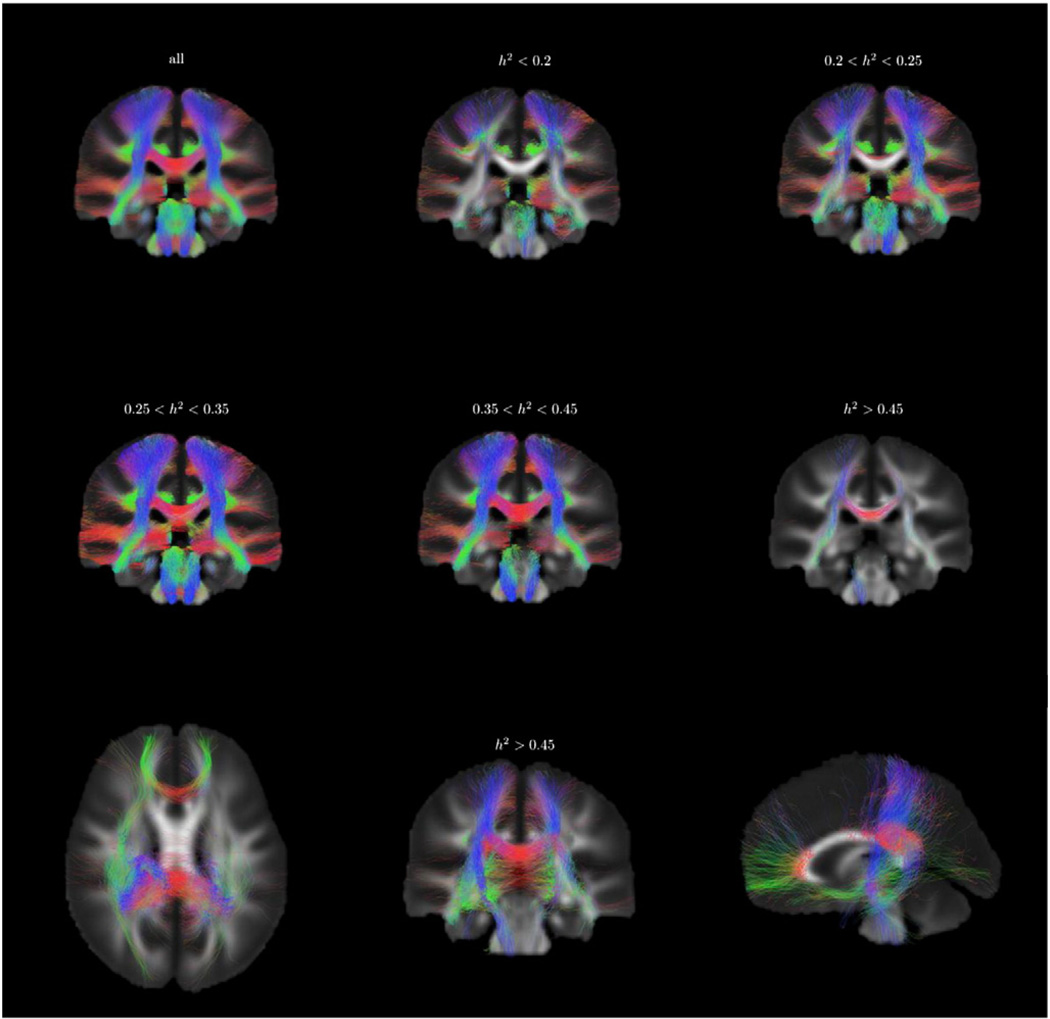

Heritable WM fiber tracts

We built a whole brain tractogram on the population average FOD template using a probabilistic fiber tracking algorithm. In total 250,000 tracts were generated, among which 122,000 were kept because both ends were located in the cortex, connecting to subcortical nuclei, or passing through the brain stem. We selected among these tracts a reliable subset with tract-average test–retest ICC greater than 0.6, comprising 98,000 tracts, which were then ranked according to their average heritability index, h2. In Fig. 12, the tractogram was binned into 6 classes according to h2, showing the WM fiber tracts with heritability ranging from below 0.2 to greater than 0.45.

Fig. 12.

Distribution of fiber tracts (test–retest reliability ICC > 0.6) from the fiber tracking results according to heritability, coronal slice of the tractogram. The sample tracts are separated by thresholding their tract-average heritability index. A projection of tracts with average h2 > 0.45 is shown in the third row.

The fibers with different heritability appeared to form different connection networks, which are shown by both voxel-based and tract-based analyses. In Fig. 12, the heritable connections (h2 > 0.45) mainly consisted of commissural fibers through genu (forceps minor) and posterior part of corpus callosum, association fibers in the right hemisphere, and right projection fibers in cortico-spinal tracts. Less heritable fiber connections are almost absent in the corpus callosum, whereas the commissural fibers transiting via the corpus callosum appeared exclusively in groups with higher heritability. These are consistent with our voxel-based finding of heritability h2 > 0.5 in corpus callosum body and genu. The heritable association and projections fibers in the right hemisphere from tract-based analysis also reflect the heritability findings in the voxel-based analysis, in which we found the right inferior fronto-occipital fasciculus, right superior longitudinal fasciculus, and right cortico-spinal tracts displayed higher heritability.